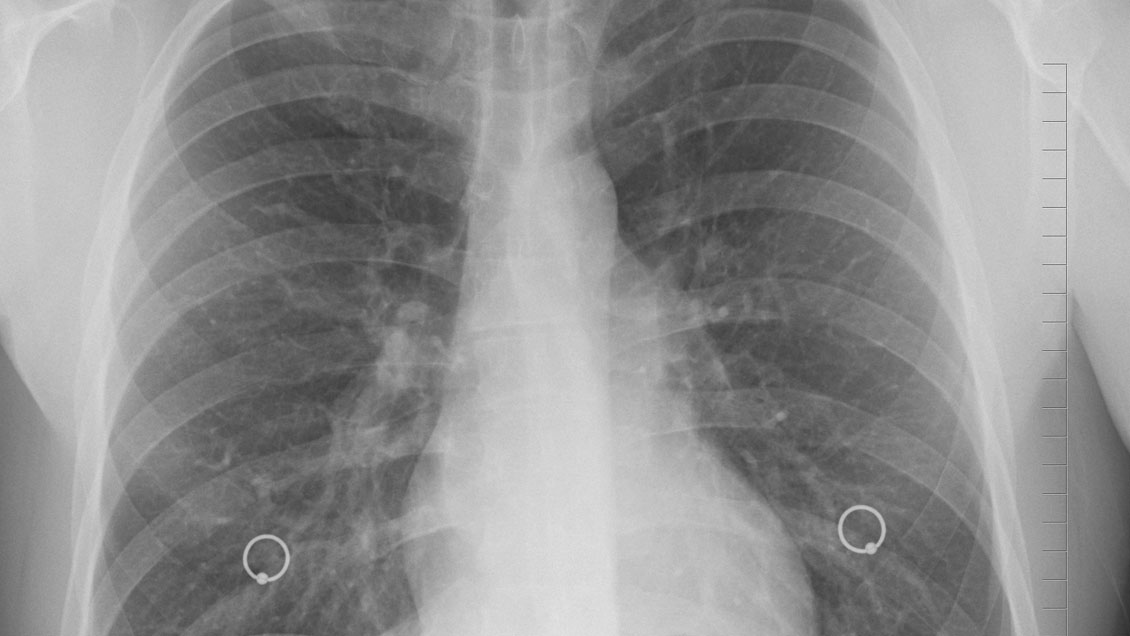

Nuevo tratamiento aumenta la supervivencia en pacientes con cáncer de pulmón

Pixabay (referencial)